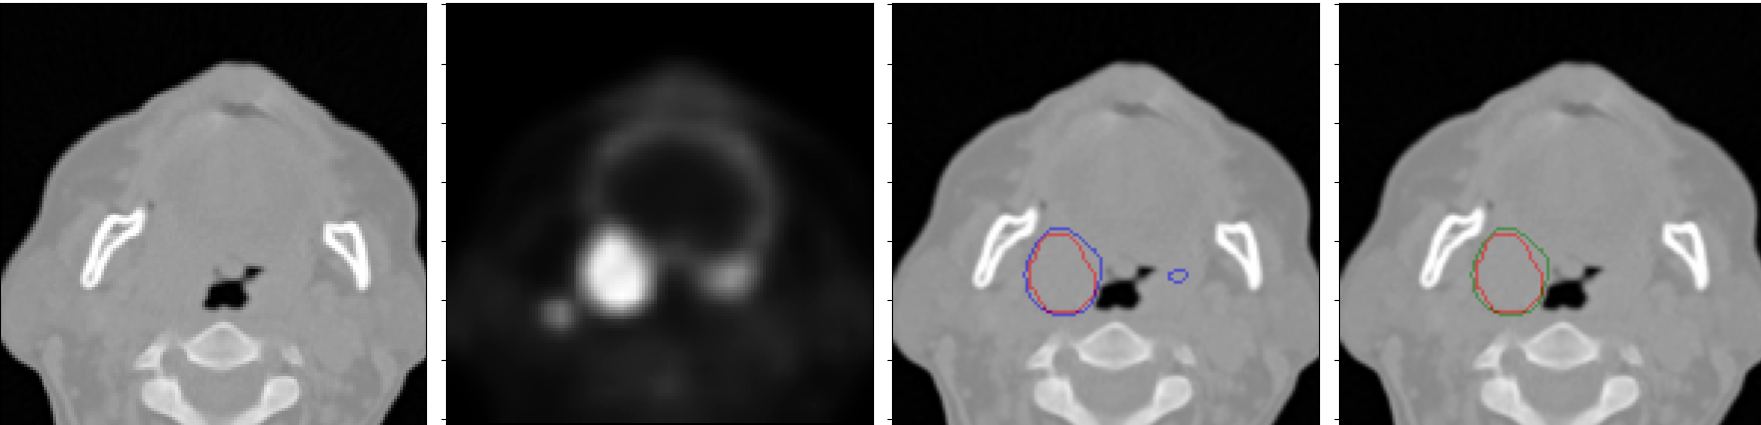

We trained the 3D NormResSE-Unet3+ on a leave-out one center, and we performed model ensembling by averaging the predictions on the test set of the 5 models trained (see Fig. 3 and Tab. 1).

An example of the predicted segmentation map, which benefited from the CRF post-processing to reduce false positives is shown in Fig. 3 (the second row).

An example of failure of our pipeline to discard false positives from true primary tumour is shown in Fig. 3 (the third row).